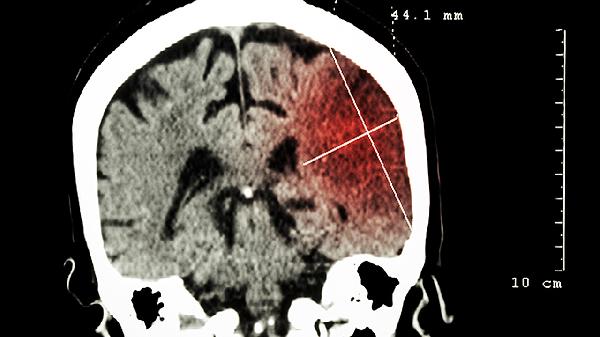

放射治疗对于那些不适合手术或手术后残留病灶的患者是一种常用的方法。该治疗可以帮助控制良性脑瘤的生长,延长患者生存时间。

对于较大或易于手术干预的良性脑瘤,外科手术是常规治疗选择。该病通过手术尽可能地完整切除,减轻压迫症状,通过获取活检样本确诊。